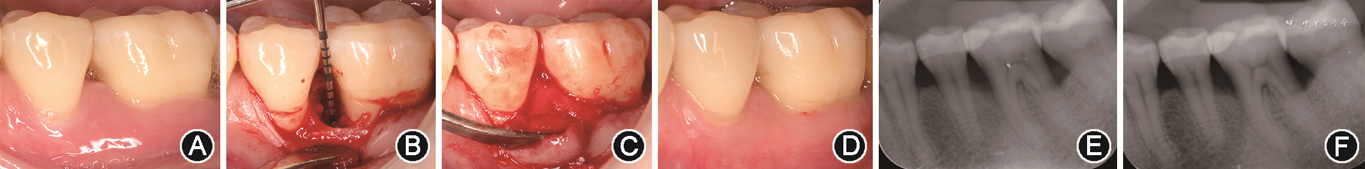

1.切口设计:牙周再生手术的切口在龈乳头区需根据邻间宽度(龈乳头基底部宽度)决定采用何种龈乳头保护切口,建议使用显微手术刀片做切口。龈乳头宽度>2 mm、基底较宽(如上前牙区)时,可采用改良龈乳头保护技术(modified papilla preservation technique,MPPT)[34](图1A,B)。具体方法:于唇颊侧龈乳头基底部做水平切口,将整个龈乳头推至舌腭侧,而颊侧瓣可进行彻底松弛后冠向复位。在邻间骨下缺损区植入再生材料后采用水平内褥式缝合减张并复位龈乳头覆盖于骨缺损区上方,使创面一期愈合,稳定下方血凝块和再生材料。但龈乳头宽度≤2 mm、基底较窄(下前牙区及磨牙区常见)时,若仍采用MPPT则可大大增加龈乳头坏死的概率,此时建议采用简化龈乳头保护瓣(simplified papilla preservation flap,SPPF)[35](图1C,D)。具体方法:于骨缺损对应的龈乳头做一斜行切口,从患牙颊侧轴角位置的龈缘切入,手术刀片始终与牙长轴平行,在颊舌向斜形切开至龈乳头顶点稍偏下方的位置(图1C),从

面观,自患牙颊侧轴角切入至邻牙接近邻面中线的位置(图1D)。以此将整个龈乳头分为包含龈乳头顶部且较大的腭侧瓣和包含较小部分龈乳头的颊侧瓣,采用该方法可较大程度改善龈乳头血供,降低移植材料暴露的概率,从而获得更多的牙周新附着和骨再生。已有文献显示,采用SPPF可获得(4.9±1.8)mm的CAL增加量,67%以上的病例始终维持一期愈合[35]。

面观;C:简化龈乳头保护瓣(SPPF)切口(红色线段)颊面观;D:SPPF切口(红色线段)

面观;E:微创手术技术翻瓣(红色虚线为切口);F:改良微创手术技术翻瓣(红色曲线为切口)

面观;E:微创手术技术翻瓣(红色虚线为切口);F:改良微创手术技术翻瓣(红色曲线为切口)在颊舌侧龈缘位置,为保留角化组织均采用沟内切口;在无牙区多行牙槽嵴顶的水平延伸切口,仅当角化龈较少,前庭较浅时,建议行稍偏舌腭侧的牙槽嵴顶切口。需确保水平切口位于角化龈上,以获得更好的初期创面封闭效果。如有必要,颊侧瓣的松弛首先推荐采用沟内延伸切口或内水平切口切开骨膜松弛。若张力仍然较大,则可在远中位置附加一道垂直切口进行减张。若仍无法做到无张力的冠向复位完全覆盖移植材料,则建议于术区两端附加两道垂直切口形成梯形瓣进一步松弛。因垂直切口可能导致瘢痕影响美观以及颊侧龈瓣的血供和稳定,临床应尽可能避免使用。选择正确的手术切口能简化手术过程,减少创伤;合适的切口使术区龈乳头、角化龈等软组织得以完整保存,这是牙周再生手术成功的关键要素,也是获得最终良好美学效果的基石,因此针对每例患者必须个性化分析,按照上述原则设计恰当的手术切口并精细地按步实施。